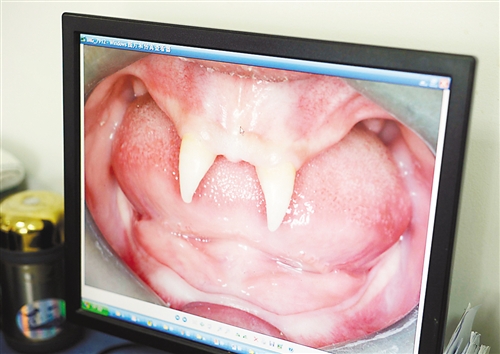

12月18日,16歲的張成(化名)從小到大,只有上顎部分有兩顆牙,看上去更像長著一對獠牙。 記者熊明攝

張成是貴州銅仁地區(qū)思南縣人,從生下來就似乎得了一種怪病,身上毛發(fā)稀少,面部發(fā)育也不好。更奇怪的是,別人家的孩子都長牙吃東西了,他卻一直長不出牙齒,最后只在上顎部分冒出兩顆比較突出且對稱的牙齒,看起來就像一對獠牙。